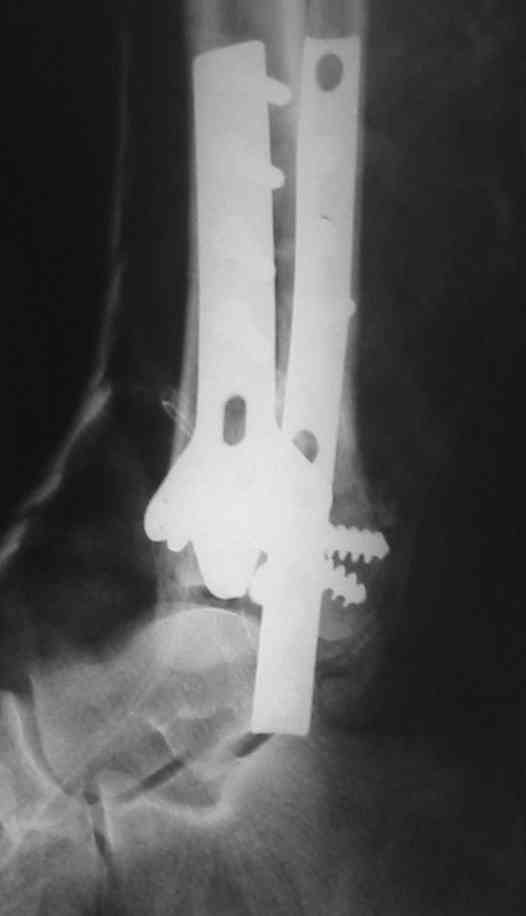

Это типичный перелом пилона, который надп лечить только открыто.Извини те что опоздал к обсуждению, но даже если вы уже оперировали больного по Илизарову это даже лучше.Посылаю картинки.

Посмотрим вроде прошло если понравится напишите расскажу как это сделать.По принципам АО кстати при поступлении сначала восстанавливают длину малоберцовой кости фиксируют пластиной 1/3 трубки потом накладывают аппарат наружной фиксации и через 7-10 дней открыто восстанавливают большеберцовую кость.С уважением Дрягин

На рентгенограммах типичный перелом пилона по типу С-3. есть опыт до 100 открытых опреаций у нас в клинике. 20 примерно в год. Принцип один -все внутрисуставные переломы нуждаются в открытой репозиции и внутренней стабильной фиксации. При поступлении КТ не надо, так как получается только нагромождение костей. Истинной картины нет. Главное восстановить длину малоберцовой кости - это ключ к успеху. При поступлении меньше всего надо думать о сосудистых расстройствах, т.к. сама операция и репозиция даже сначала частичная даёт улучшение сосудитых нарушений. Причём очень быстро. Операция в 2этапа. При поступлении доступ позади наружной лодыжки, причём обязательно. После этого репозиция малоберцовой кости и фиксация пластиной 1/3 трубки под винт 3,5. Дренаж и любой аппарат наружной фиксации. Затем после спадения отёка на 5-7-10 день аппрат снимается и дугообразный разрез спереди от медиальной лодыжки 10-12 см. Главной чтобы расстояние между 1 и вторым разрезом было не меньше 7-8 см. Тогда не будет некрозов лоскутов. Таранная кость используется как матрица на неё укладываются отломки и фиксируются пицами. Ренг-контроль. Отломки лежат все отдельно, но ничего не высыпется. При переломах С-3 всегда нужна костная пластика (из крыла). Фиксация пластиной лист клевера простой или LCP. Гипс не нужен. Дренаж до 48 часов. Операция длится 3-4 часа обязательно без жгута. Посылаю примерно такой же случай.

Посылаю результат лечения предыдущего больного через год.